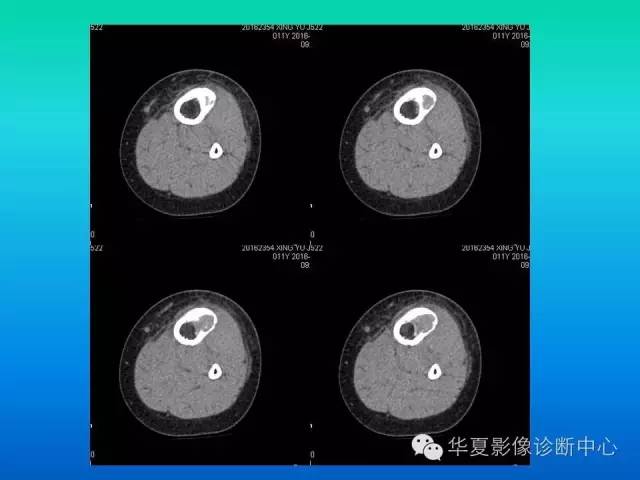

【病例】胫骨非骨化性纤维瘤1例CT影像表现

患者:男,11岁,腿疼

病理结果【非骨化性纤维瘤】

CT:

1)病灶呈圆形或卵圆形囊状低密度区,有分房时形似蜂窝状或皂泡状。

2)边界清晰,有线形骨硬化带环绕,局部骨皮质稍膨胀变薄,但很少突向骨外。

3)病灶常位于干骺端,距骨骺线3~4厘米处,呈偏心性,多在皮质下。